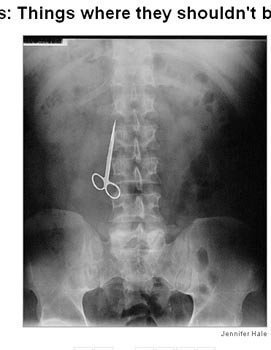

Hai trường hợp trên, các bác sĩ đã để quên kéo trong bụng của bệnh nhân sau khi phẫu thuật. Trường hợp thứ hai, trong cơ thể bệnh nhân có tới 2 cái kéo.